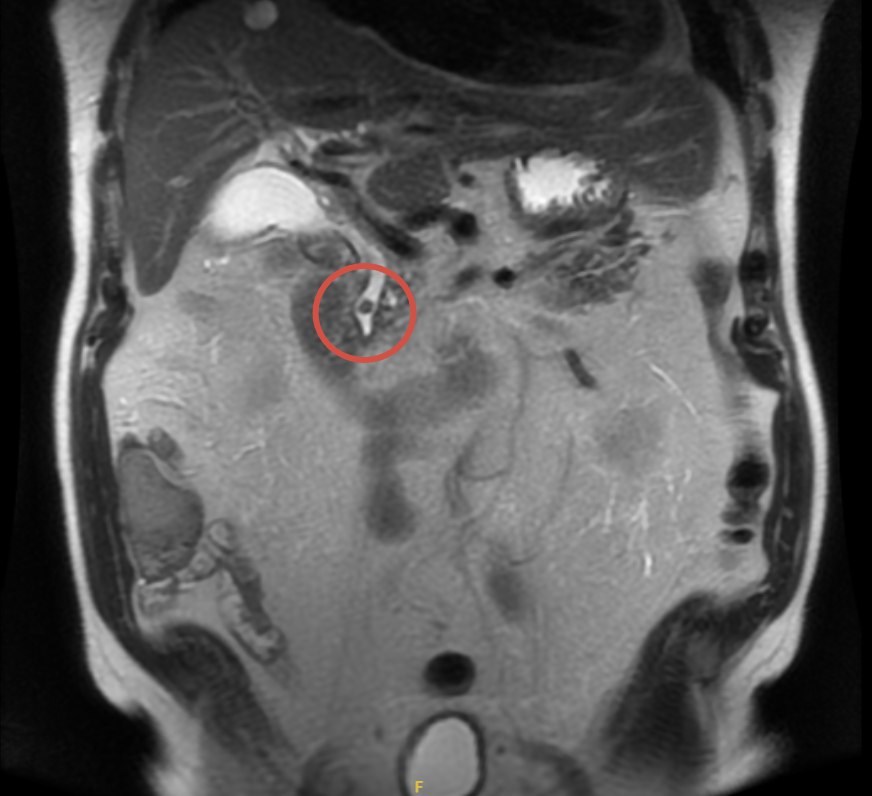

МРХПГ

• Конкремент до 7 мм в интрапанкреатическом отделе холедоха

• Минимальное расширение общего желчного протока (10–11 мм)

• Желчный пузырь без камней